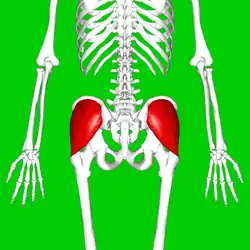

Position of gluteus medius muscle (shown in red). Posterior view. | |

Position of gluteus medius muscle (shown in red). Hip bone is shown in semi-transparent.